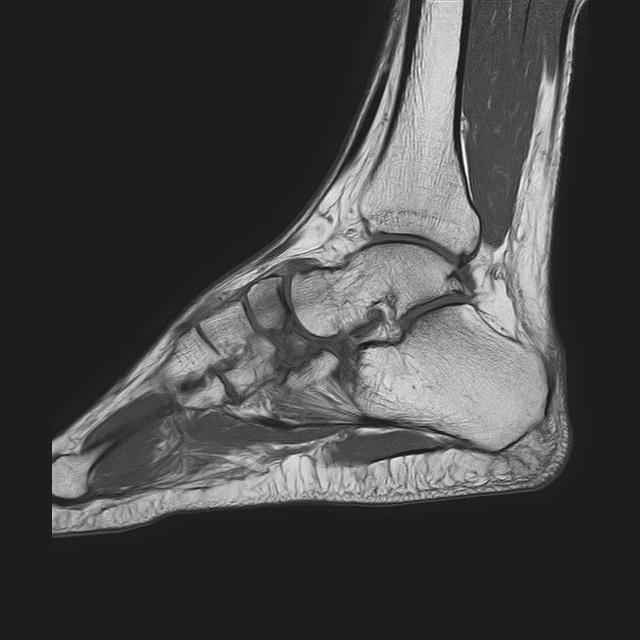

Дорогие коллеги, Мужчина 36 лет, пострадал около 8 месяцев назад в ДТП (водитель мотоцикла).

Подтаранный вывих лечили гипсовой лонгетой. Недиагностированным остался перелом ладьевидной кости, который беспокоит в настоящее время. Аваскулярный некроз кости, похоже. Добавил наиболее значимые снимки, на мой взгляд.